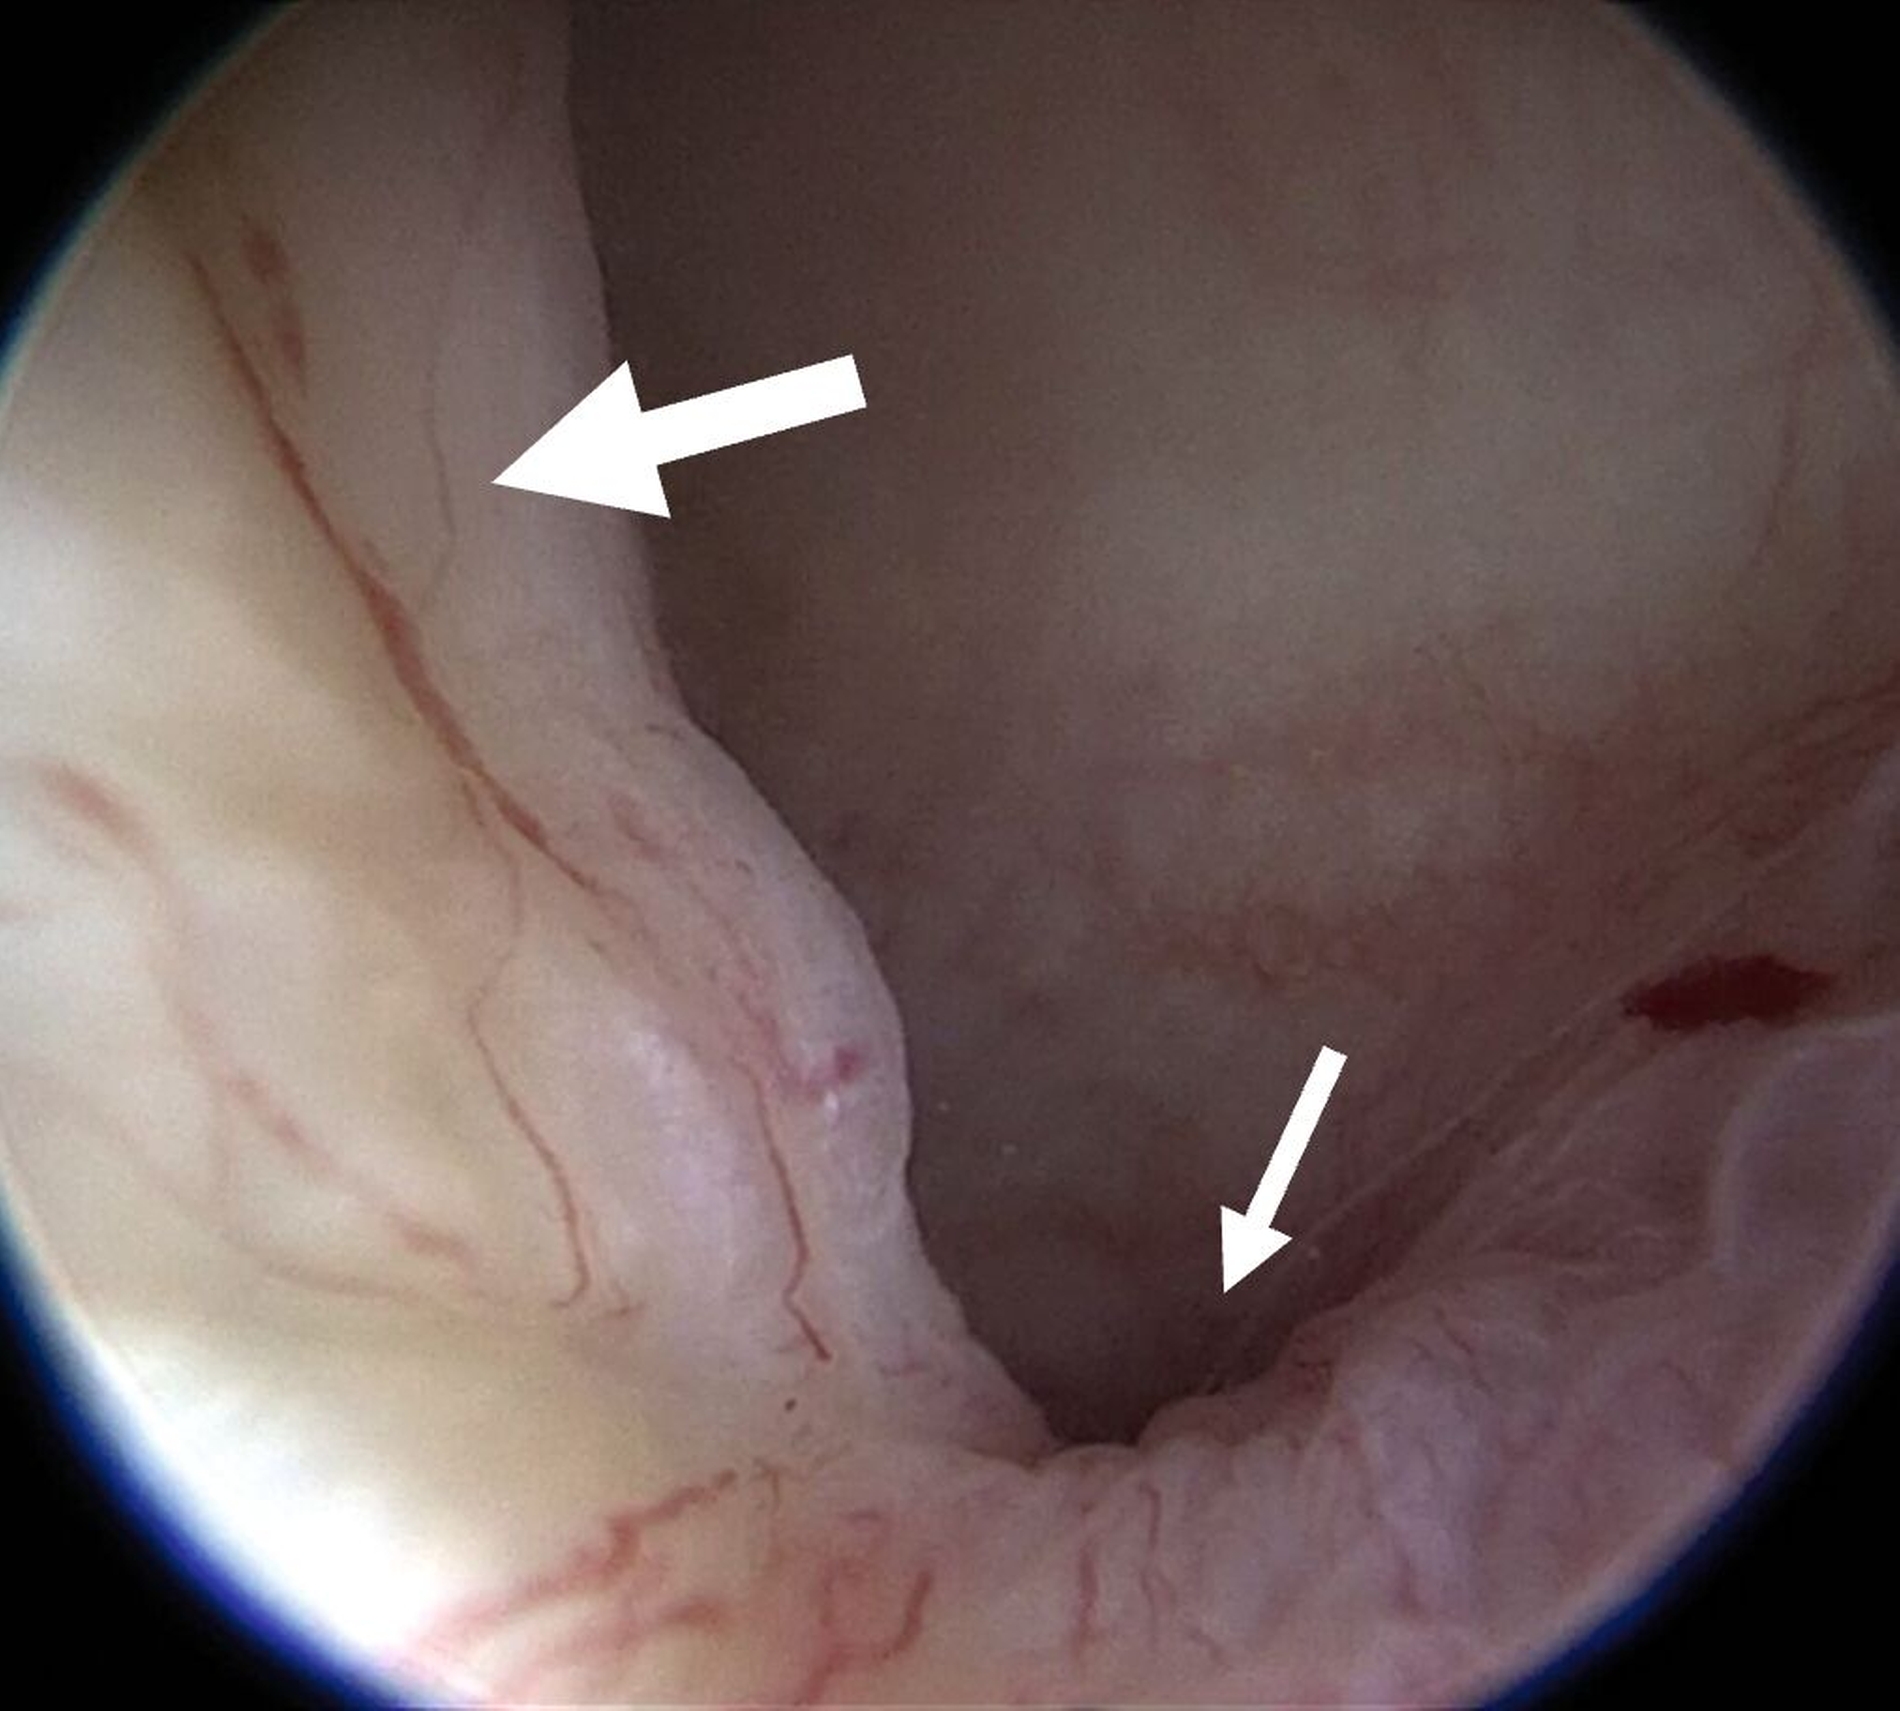

Eine Entzündung im Bereich der Gelenkkapsel (Synovitis) stellt eine häufige Ursache für arthrogen bedingte Beschwerden dar [Mercuri et al., 2025]. Neben der Darstellung des Gelenks und der Behandlung von Pathologien beruht ein positiver Effekt der Arthroskopie auf der Lavage des Gelenks. Dadurch können zum Beispiel proinflammatorische Mediatoren entfernt und intraartikuläre Adhäsionen gelöst werden [Soni, 2019]. Abbildung 2 zeigt die intraoperativen Befunde von zwei Patienten. Es wird jeweils der Übergang zwischen dem hinteren Aufhängungsband und der pars posterior des Discus articularis dargestellt.